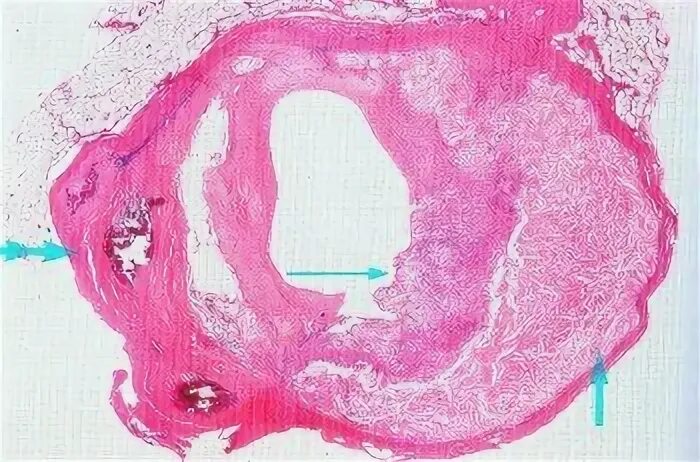

Атеросклероз аорты препарат